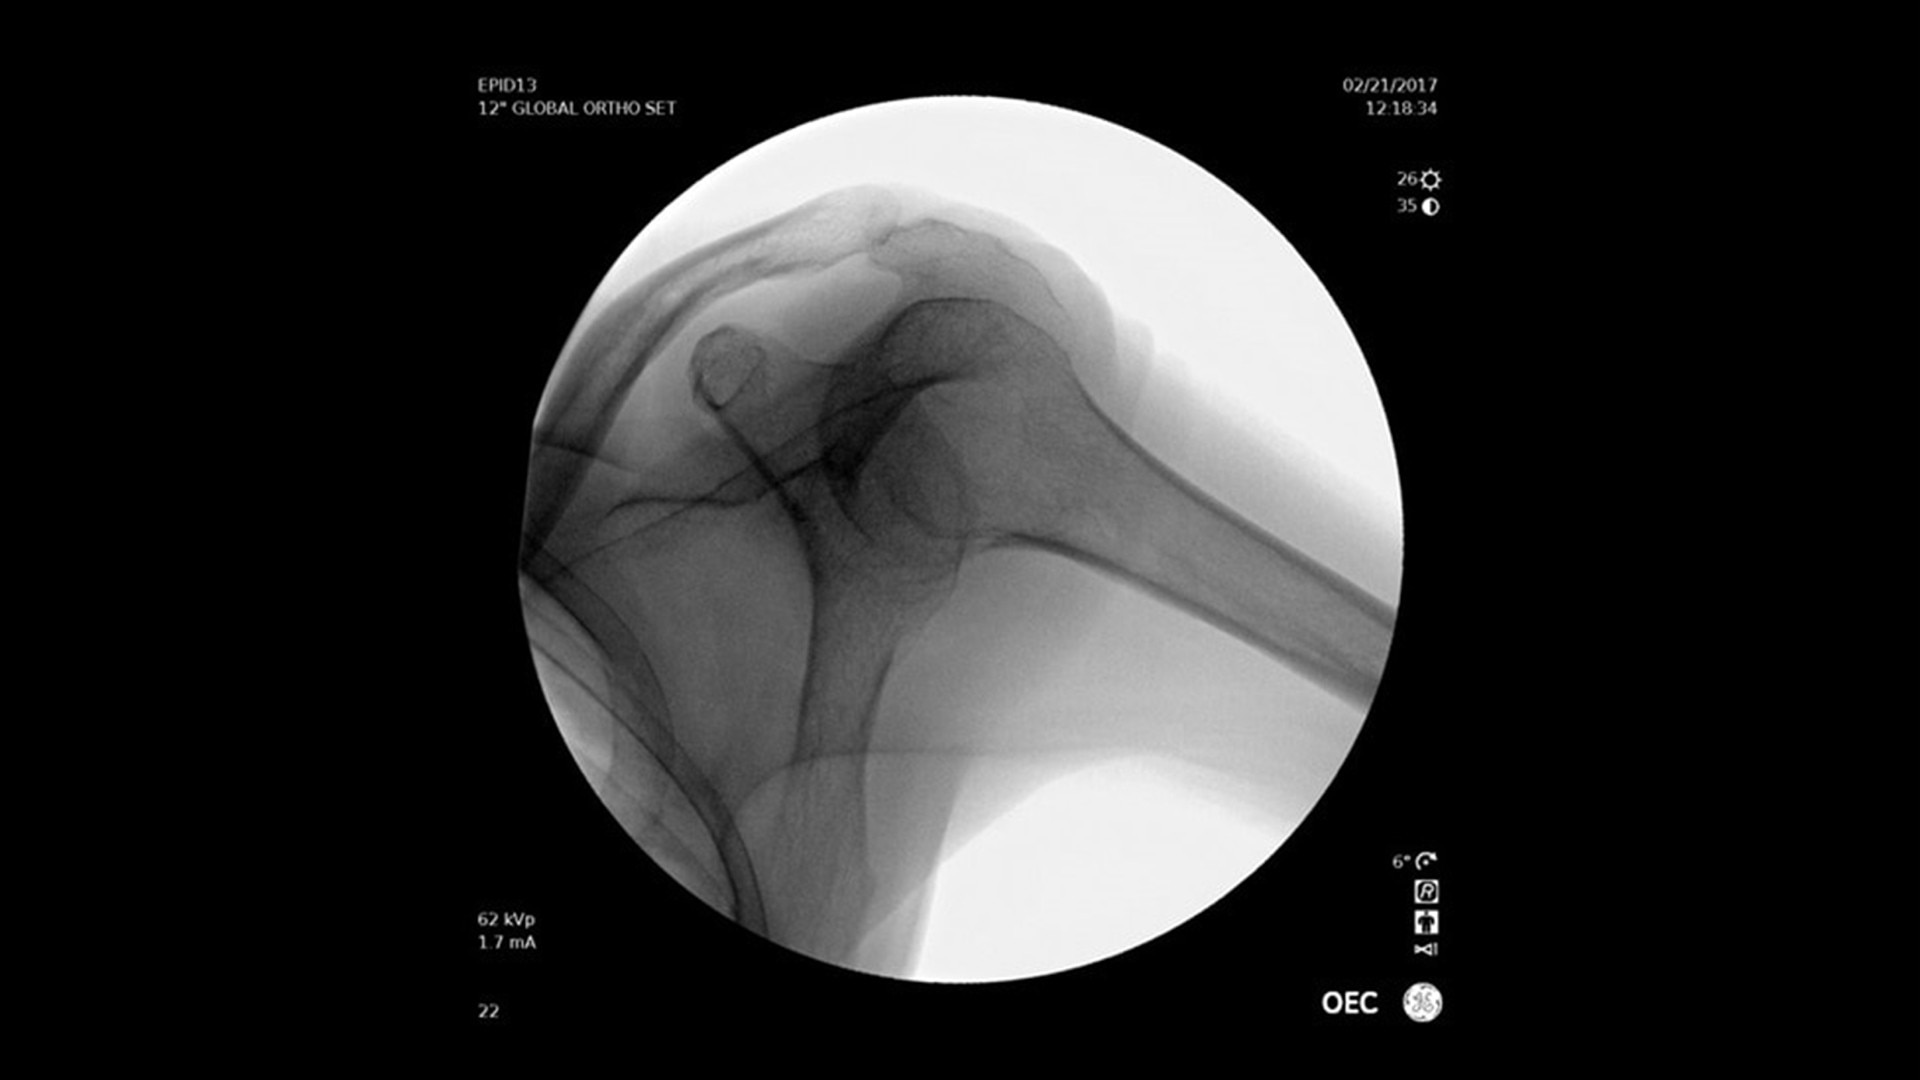

OEC Elite

Renommierte Bildqualität mit verbesserter Benutzerfreundlichkeit und Effizienz.

Der mobile C-Bogen OEC Elite unterstützt Sie mit leistungsstarker Technologie und intuitiver Bedienung – für mehr Effizienz in unterschiedlichsten chirurgischen Anwendungen. Profitieren Sie von:

• Hervorragender Bildqualität für präzise intraoperative Entscheidungen

Vielseitig einsetzbar – ideal für orthopädische, gastrointestinale, endoskopische, urologische, neurologische und vaskuläre Eingriffe sowie für die Intensiv- und Notfallmedizin.

Bildqualität und innovative Funktionen

Der OEC Elite unterstützt Ihr OP-Team mit fortschrittlicher Bildverarbeitung, die sich dynamisch an klinische Anforderungen anpasst. So entstehen jederzeit präzise und detailreiche Bilder.

Renommierte Bildgebung – mehr sehen, mit weniger Dosis.

Nutzen Sie innovative Funktionen wie Live-Zoom, Digital Pen und vorkonfigurierte Bildprofile – darunter Pädiatrie, General HD und die optionale Bolus-Verfolgung – für eine präzise und schonende Bildgebung.

Im Vergleich zu herkömmlichen Monoblock-C-Bögen ermöglicht der OEC Elite eine bis zu 22 % größere Darstellung anatomischer Strukturen und eine nähere Positionierung des Detektors an der Patientenanatomie.